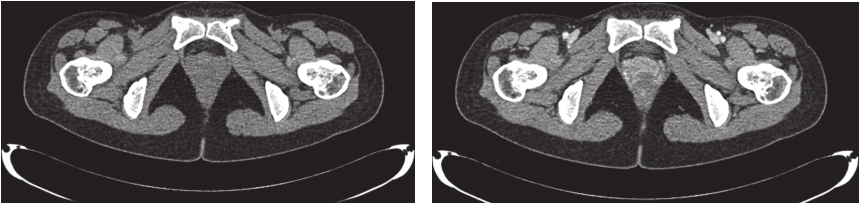

完善经直肠超声:直肠下段及肛管前壁距肛门1cm处可见不均匀低回声,大小约为4.3cm×3.7cm,内部回声不均,内部血流丰富、紊乱,可引出动脉频谱;肿瘤位于腹膜反折以下;耻骨直肠肌、肛门外括约肌完整。经腹超声见盆腔不均匀低回声,大小约5.9cm×4.8cm,与阴道分界不清。经会阴超声见盆腔不均匀低回声,大小约5.2cm×5.5cm,前方距皮肤约0.2cm,边界欠清,形态不规则,内血流信号丰富,可引出动脉频谱。完善PET-CT示:阴道下段与直肠前壁见类圆形肿物,大小约5.0cm×3.5cm×5.9cm,密度稍欠均匀,肿物与阴道、直肠前壁均分界不清,局部突向外阴。术前评估为潜在可切除性直肠GIST,考虑到肿物较大且与周围组织器官关系密切,直接切除有联合脏器切除的可能,且难以保全阴道和肛门功能,遂决定行术前靶向药物治疗。患者从2016年4月15日起,开始口服甲磺酸伊马替尼,400mg/d。此后规律复查,伊马替尼治疗1个月后复查增强CT(图2):直肠下段与阴道间可见类圆形混杂密度影,范围大致约4.2cm×2.5cm×2.6cm,病灶密度不均,其内可见液性密度区,增强扫描实性成分明显强化,病灶局部与直肠前壁及阴道后壁分界不清。对比首诊盆腔MRI,病灶较前缩小(Choi标准:PR状态)。伊马替尼治疗4个月后复查增强CT(图3):直肠下段与阴道间可见类圆形低密度病灶,大小约3.5cm×2.3cm×1.8cm,增强扫描可见轻度强化,病灶局部与直肠前壁及阴道后壁分界不清。对比前次复查:病灶较前略缩小(Choi标准:PR状态)。伊马替尼治疗6个月后复查增强CT(图4):直肠下段与阴道间可见类圆形低密度病灶,大小约3.9cm×2.1cm×1.9cm,增强扫描可见轻度强化,病灶局部与直肠前壁及阴道后壁分界不清。对比前片,病灶较前无明显改变(Choi标准:维持PR状态)。考虑患者术前靶向治疗已进行6月余,且药物治疗效果已达最大化,建议患者接受手术治疗。2016年11月1日门诊以“胃肠间质瘤,靶向治疗后”收入北京大学人民医院胃肠外科。

图3 伊马替尼术前治疗4个月后增强CT表现

引自:胃肠间质瘤典型病例诊治与解析.第1版.ISBN:978-7-117-30146-6.主编:陶凯雄 曹 晖